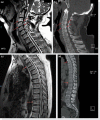

Spinal cord injuries are amongst the most dangerous injuries, leading to high mortality and morbidity. Injured patients are occasionally faced with life-threatening complications and quality-of-life changing neurological deficits. Thoracic and cervical spinal segments are the most effected sites of injury and a wide range of complications including paraplegia, respiratory and cardiovascular compromise secondary to autonomic dysfunction or tetraplegia may ensue. We aim to draw attention to the progressive nature of the neurological deficits in a patient admitted asymptomatically. Also, we would like to discuss the importance of swift diagnosis and management in such patients. In asymptomatic patients in whom no fractures are diagnosed with CT scans, a neurological examination should be repeated several times to exclude any neurological injuries that were missed. MRI should be ordered in an emergency setting even though it is not frequently used as a diagnostic modality. This should be done especially in patients without any fractures on CT but with neurological signs.